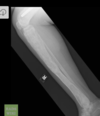

Fratura do platô tibial lateral - Schatzker tipo 2 (traço de fratura + depressão do plato lateral).